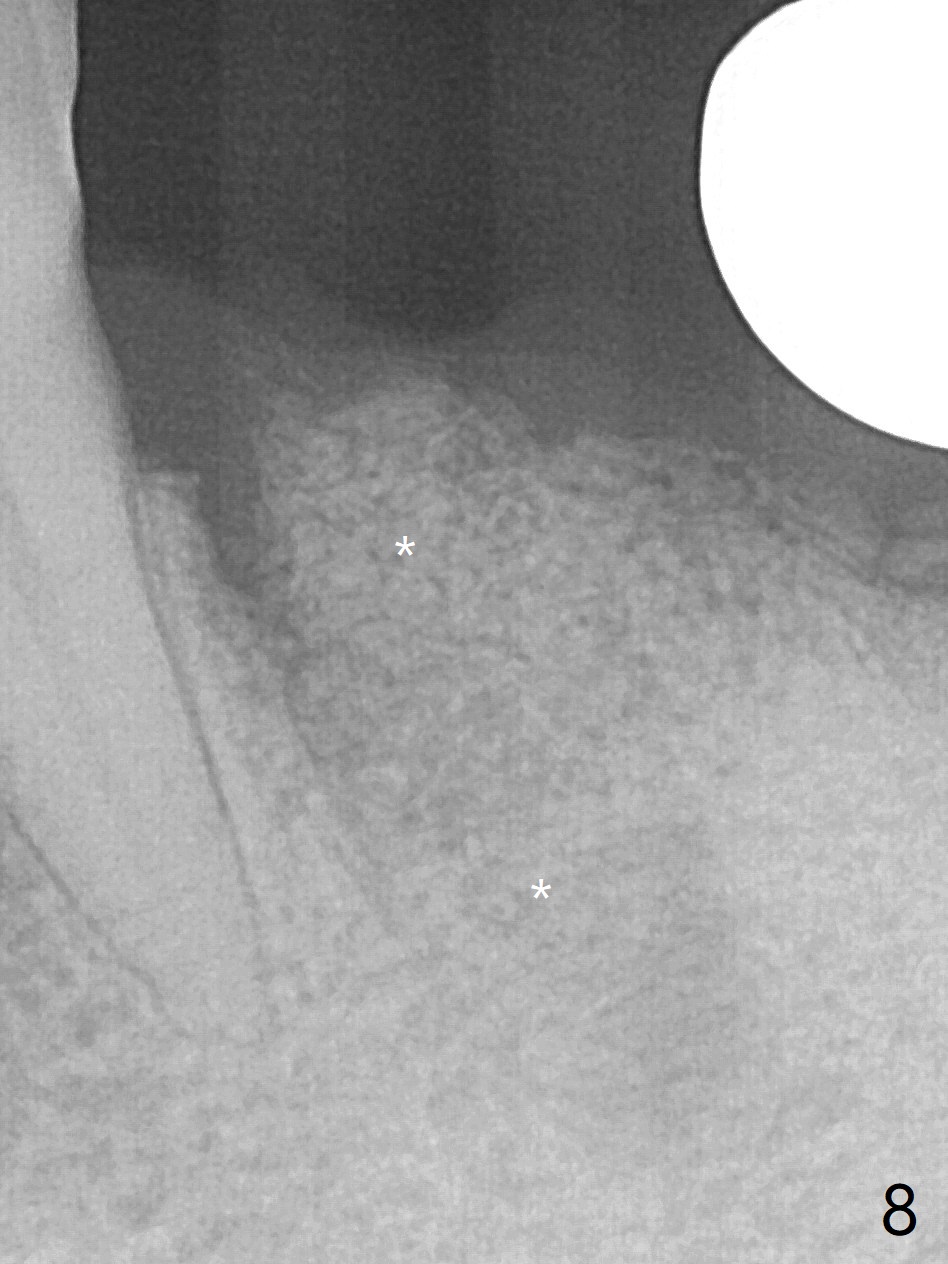

A 73-year-old man with history of stroke presented to office with #20 chewing pain 2 years ago (Fig.1). When he returns today, the tooth #20 has lost, while #21 has mobility (Fig.2), torus mandibularis (Fig.3 *) and severe bone loss, as related to Class V defect (Fig.4). As expected, the buccal plate is lost, the buccal gingiva blanching and bulging due to a curette underneath (Fig.5 *). After placement of allograft in the socket (Fig.6,8 *), a 8x8 mm BioXclude and 4-0 PGA suture are used to close the socket (Fig.7). Periodontal dressing stays in place 10 days postop (Fig.9). The patient is pleased with hemostasis. He is going to return his home state.